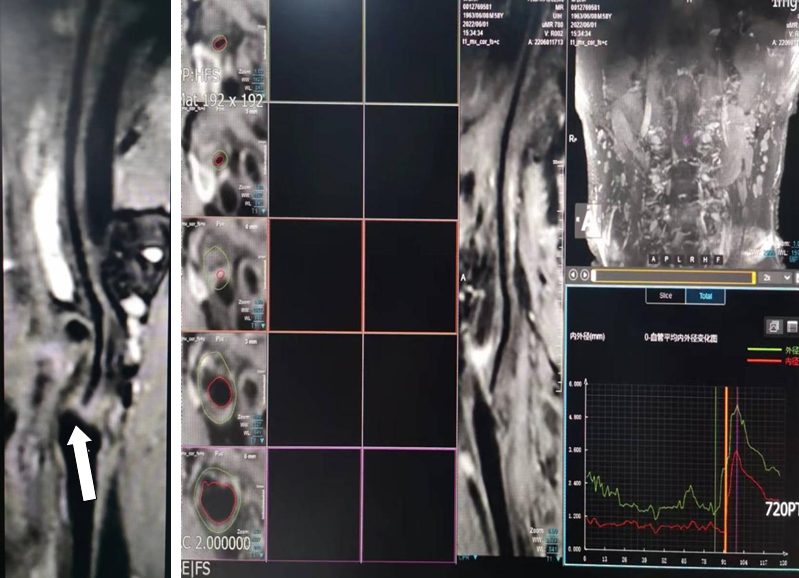

为进一步明确患者病情,卒中中心团队立即联合放射科等多学科进行病例讨论,在放射科学科带头人刘春玲主任、黄志明主任会诊评估后,于当日安排患者进行了左颈内动脉3.0T磁共振高分辨血管壁成像检查,图像清晰显示患者左侧颈内动脉起始部由于粥样硬化斑块导致的短节段次全闭塞,以远段管腔虽细小却清晰可见,经过放射科专业组团队与卒中团队联合会诊,对闭塞位置、范围及介入可行性进行了准确评估,随后卒中团队通过介入手术置入支架顺利为患者开通了左侧颈内动脉,及时阻止了脑组织的进一步缺血,患者恢复良好。

MRI高分辨血管壁成像